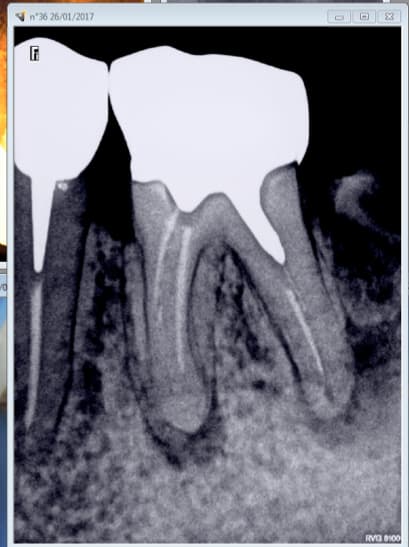

Endo ok, inlay core ok, ceram ok. -)

Made in France. -)

Je te rassure le travail initial était tout made in France. Cette dent était Vraisemblablement difficile à traiter et le confrère a fait ce qu'il a pu.

Et dire que j'en remets une couche avec de la prothèse d'import. Il n'a vraiment pas de bol le patient hein ? -)))

Oh mais que vois je ? Du tout made in France en bas aussi ? Comme c'est difficile l'endo en France hein ? -))))

Controle des prix = merde. Notre travail est praticien et temps dépendant. Un dentiste A ne fait pas forcément le meme travail qu'un dentiste B.